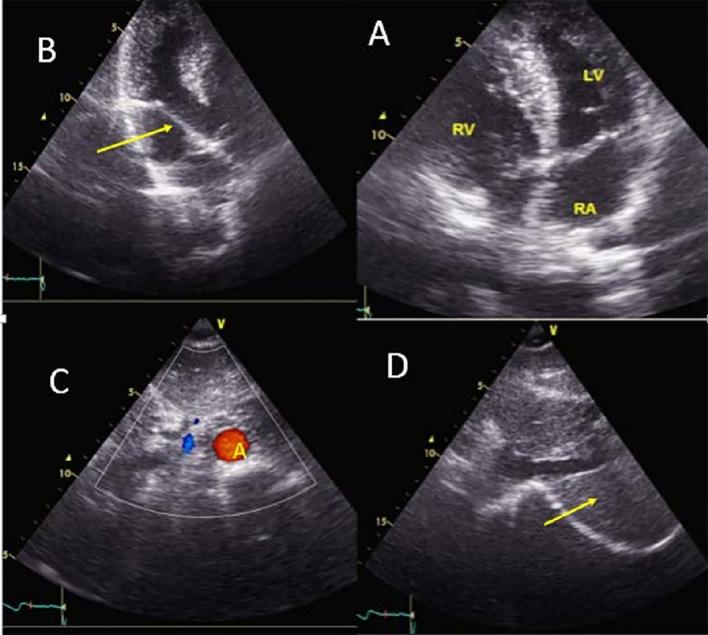

Situs inversus with levocardia and congenitally corrected transposition of the great arteries represents a relatively very rare congenital condition and most patients are diagnosed in infancy or early age. This case report describes a 35-year old man with congenitally corrected transposition of the great arteries which presented with a five month history of exertional dyspnea. A diagnosis was confirmed by transesophageal echocardiogram, showing situs inversus, levocardia, atrioventricular and ventriculoarterial discordance. He underwent physiologic repair, and was discharged thirty five days after the operation, in a good general condition. Although management of the corrected transposition of the great arteries patients remains controversial, the recommendation is that physiologic repair may be the procedure of choice for some patients, particularly complicated cases.

镜像右位心伴左位心及先天性矫正型大动脉转位是一种相对非常罕见的先天性疾病,大多数患者在婴儿期或幼年时被诊断出来。本病例报告描述了一名35岁男性,患有先天性矫正型大动脉转位,出现劳力性呼吸困难5个月病史。经食管超声心动图确诊,显示镜像右位心、左位心、房室和心室动脉不一致。他接受了生理性修复手术,术后35天出院,全身状况良好。尽管先天性矫正型大动脉转位患者的治疗仍存在争议,但建议生理性修复可能是某些患者,尤其是复杂病例的首选手术方式。